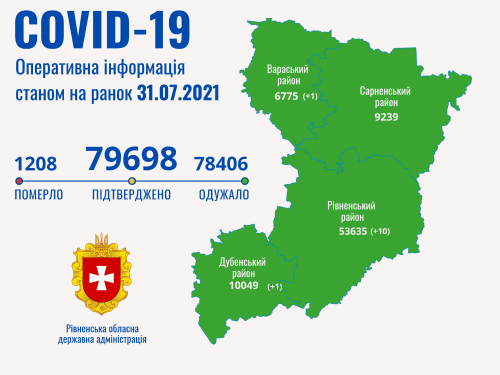

Коронавірус повертається: як стрімко зростає кількість хворих на Рівненщині (ВІДЕО)

Пів тисячі - у важкому стані, 9 жителів Рівненщини померли за добу від коронавірусу